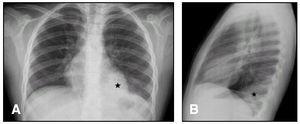

La radiografía de tórax, en inspiración y espiración (fig. 1), evidenció consolidación en lóbulo inferior izquierdo (asterisco), sin adenopatías mediastínicas ni signos de atrapamiento aéreo que sugirieran cuerpo extraño. En la TC torácica helicoidal sin contraste se confirmó una neumonía-atelectasia en lóbulo inferior izquierdo, sin derrame, adenopatías ni alteraciones en árbol traqueobronquial. El estudio de angio-RM reveló una consolidación en lóbulo inferior izquierdo, hacia la que se dirige un vaso (flecha) originado en la aorta torácica descendente, por encima del orificio diafragmático y que constituye un vaso arterial nutricio (fig. 2).

Figura 1. A) Tórax. B)Tórax lateral.